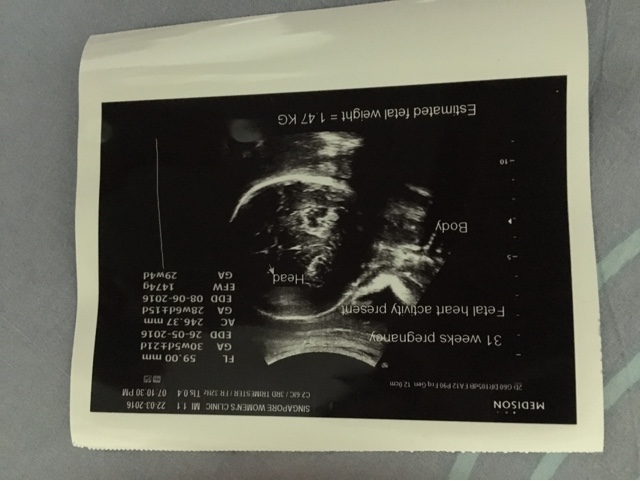

我的宝啊!你要在妈妈的堡垒里茁壮健康地长大呀!你的成长进度有点赶不上呀!是不是妈妈让你吸取的营养不足够啊?妈妈的体重也没增加多少,反而又比十天前跌了三百克,仅有59.9公斤,比第一次的产检多了两公斤多而已,我一直百思不解,我没特意吃少啊,还是照着平常的量吃啊!然而,却还是非常的不达标。